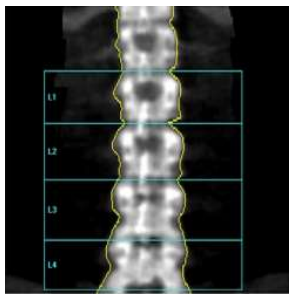

Assinale a alternativa que apresenta qual o erro na aquisição da imagem abaixo.

Assinale a alternativa correta.